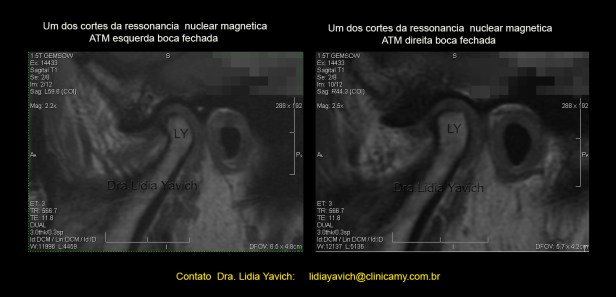

Um dos cortes da ressonância nuclear magnética mostrando a assimetria das cabeças mandibulares, e a alteração do eixo de crescimento do lado esquerdo.

Um dos cortes da ressonância nuclear magnética mostrando a assimetria das cabeças mandibulares, e a alteração do eixo de crescimento do lado esquerdo.

Os discos articulares se encontram luxados anteriormente com redução nos cortes da ressonância em boca aberta (não incluídos nesta publicação).

O objetivo principal neste caso é a descompressão e equilíbrio tridimensional dos músculos mastigatórios. As assimetrias estruturais provocadas pelo traumatismo não podem ser modificadas, mas o equilíbrio muscular sim.